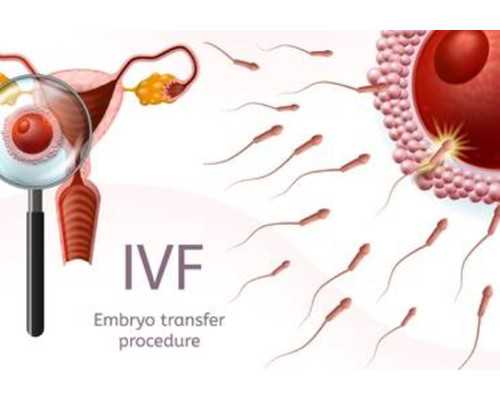

試管嬰兒移植前雌二醇3000

1.做試管嬰兒準備移植抽血雌二醇多少才可以合格

3.做試管嬰兒準備移植抽血雌二醇多少才可以合格

4.做試管嬰兒準備移植抽血雌二醇多少才可以合格

7.做試管嬰兒準備移植抽血雌二醇多少才可以合格

8.做試管嬰兒準備移植抽血雌二醇多少才可以合格

9.做試管嬰兒準備移植抽血雌二醇多少才可以合格

10.做試管嬰兒準備移植抽血雌二醇多少才可以合格

4.做試管嬰兒準備移植抽血雌二醇多少才可以合格